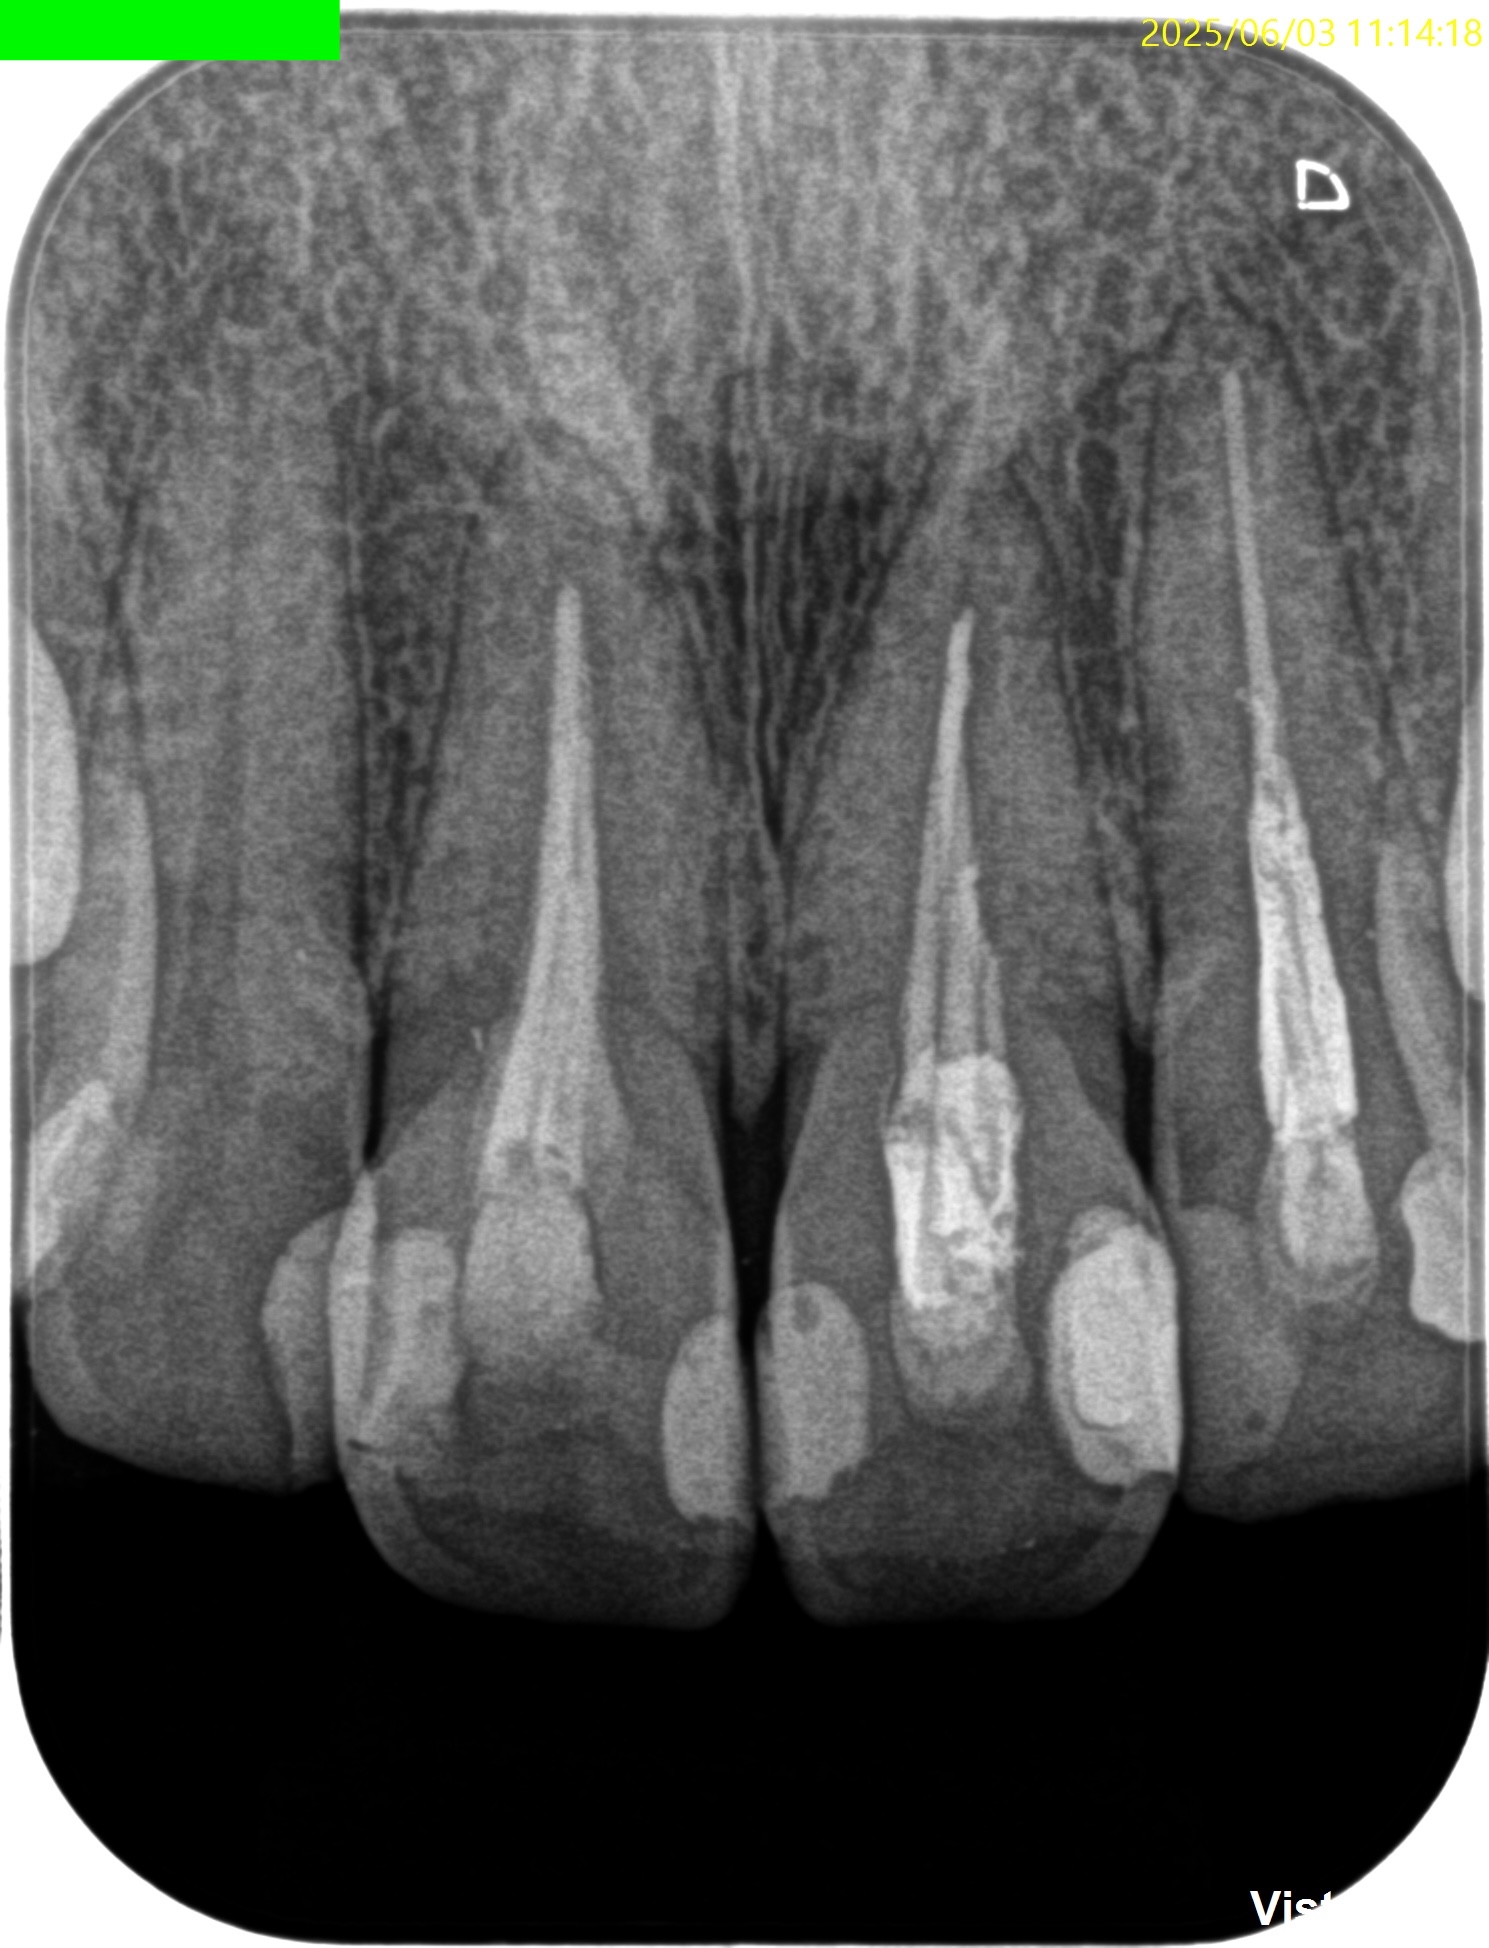

PA(2025.6.3)

#8,9,10ともに全く根管治療が不適切としか言いようがない。

#8はForamen付近の形成が太そうだ。

CBCT(2025.6.3)

#8はApexが歯槽骨からはみ出ている。

PA所見から考察するに、再治療よりも外科治療だろう。